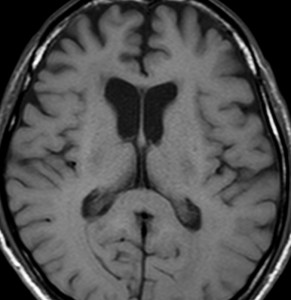

2001年に無症状で偶然発見された右辺縁回の限局性星細胞腫 well-deliniated or localized astrocytomaと呼ばれるものです。非常に限局性で,T2で強い高信号になりT2-FLAIR mismatch signがあり,T1では低信号でガドリニウム増強されない典型的画像です。

腫瘍が発見されてから2年半で少し増大したので,開頭手術で全摘出 gross total removal しました。ドロドロの柔らかい腫瘍でしたから,その部分のみを摘出して,周囲の脳には手を付けませんでした。